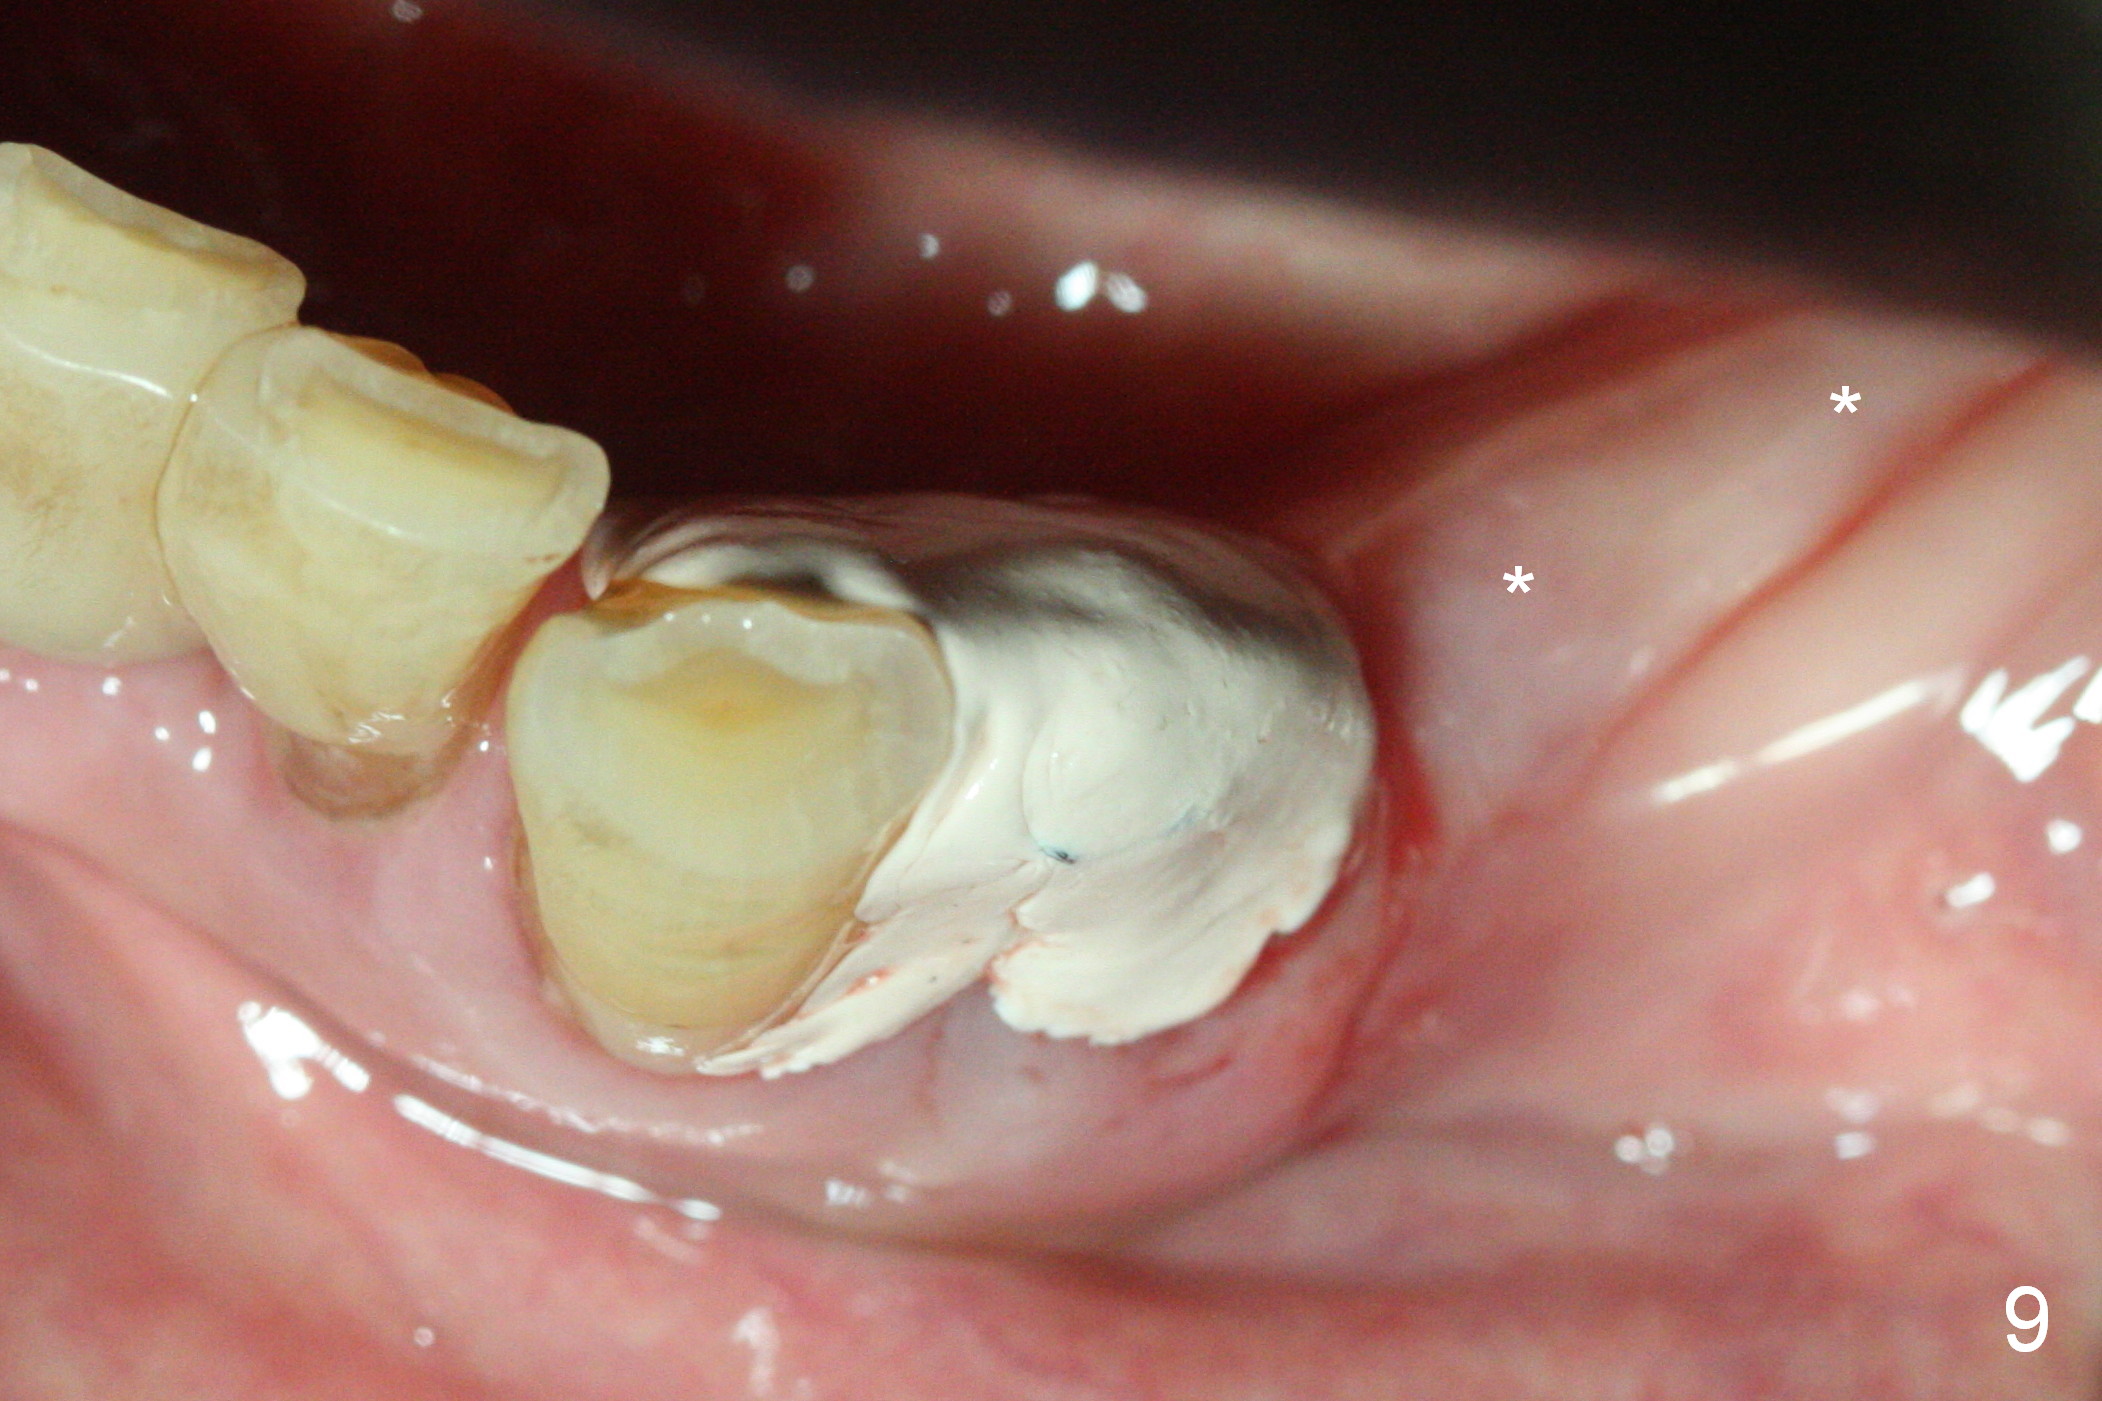

A 72-year-old man presents to clinic for implants because of pain associated with wearing the lower partial. The teeth #21, 24, 25 and 31 seem to be non-salvageable and are going to be replaced by implants so that the lower RPD can be reused (Fig.1). The edentulous ridge is atrophic (Fig.9 *). The upper complete denture appears to be functional. Since the tooth #21 is symptomatic (Fig.2) and the patient has chronic TMJ dislocation, the affected tooth is extracted first (Without antibiotic socket treatment) for immediate implant (Fig.3 (1.5 mm drill (placed more lingually)). The lower RPD is used as a surgical guide (Fig.4 (3 mm drill in place)). When a 3.8x16 mm implant is placed with bone graft (Fig.5 *), the underlying neurovascular bundle is undetected. A small field of panoramic X-ray is retaken; it seems that there is enough clearance from the Mental Foramen (Fig.2,6,7 (red dashed line)) and the Incisive Canal (pink dashed line). The implant is then placed 2 mm more apically (Fig.7) to reduce the chance of periimplantitis since the buccal plate is lost. A 5.5x5(5) mm abutment is placed (Fig.5) with more graft. The access of the abutment is left open so that a part of periodontal dressing is inserted for additional retention (Fig.8,9). The RPD is placed back for adaptation of the dressing. The patient is advised not to wear the RPD postop to reduce micromovement.

The patient returns 2 days postop because of hemorrhage (Fig.10,11 * after removal of loose periodontal dressing). Periodontal dressing is repacked (Fig.12). The hemorrhage may be due to incomplete removal of granulation tissue or invasion of the Incisive vessel intraoperatively, although there is no pain or paresthesia postop. Soft food is recommended without the upper complete denture. A provisional is fabricated (Fig.14 P) nearly 3 months postop (after changing the 5.5x5(5) mm abutment to 4.5x5(4) mm, Fig.13) when an implant is being place is #31.